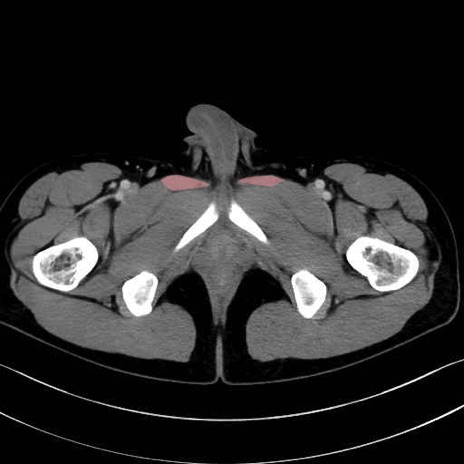

長内転筋(Adductor longus muscle)のCT画像の解剖

長内転筋 (Adductor longus)